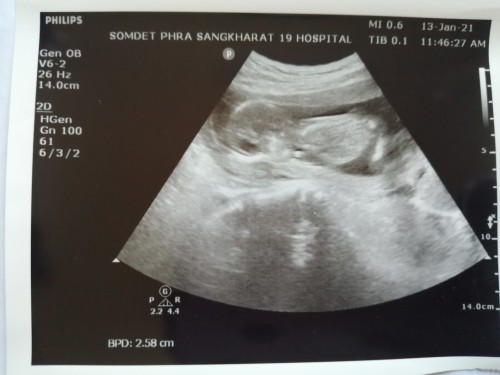

บ้านนี้20วีค ยังไม่รู้เพศเลยค่ะ